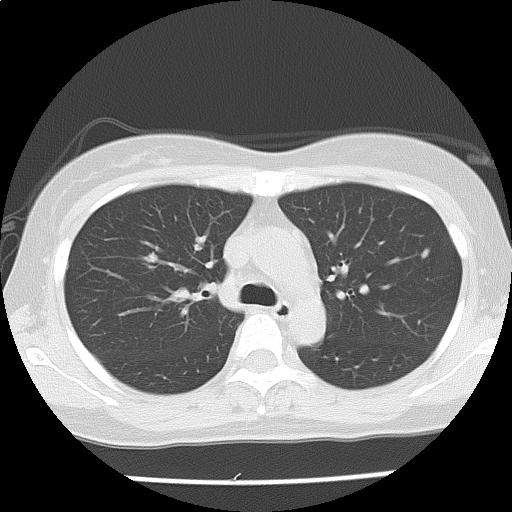

両肺に径数 mm~約9 mm の結節が多発しており(添付画像以外にも認める)、辺縁不整を認める。

多発肺転移の可能性をまず除外する必要があり、原発としては乳癌、膵癌などと考える。

悪性が否定的な場合には、感染症、血管炎、サルコイドーシスなども鑑別に挙げられる。

多発肺結節・縦隔リンパ節腫大:r/o 多発肺転移